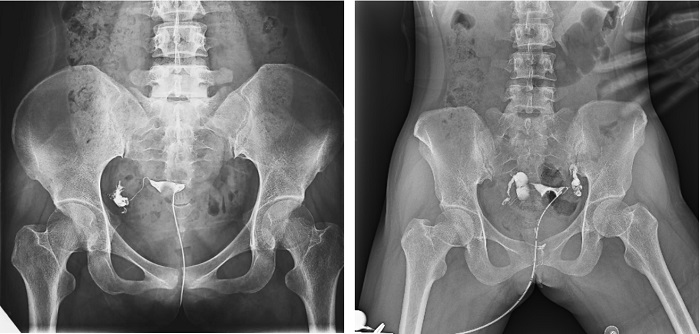

子宮輸卵管造影檢查損傷小,準(zhǔn)確率高,是婦科檢查的常用方法。利用動(dòng)態(tài)DRF進(jìn)行子宮輸卵管造影檢查,大大超越了過去的檢查技術(shù),更加精準(zhǔn)高效。動(dòng)態(tài)DRF矩形采集面積大,一次曝光即可顯示整個(gè)盆腔,大幅減少觀察時(shí)間,可控的瞬時(shí)照射避免受檢者吸收過多X線,對(duì)育齡期女性檢查尤為重要??稍谠煊皠┝鲃?dòng)的過程中完成拍片,抓拍到關(guān)鍵圖像,幫助醫(yī)生更加清楚地了解到管腔的具體通暢情況及堵塞部位,提高診斷的精準(zhǔn)性。

▲輸卵管造影

普利德動(dòng)態(tài)平板DRF床體智能化程度更高,在進(jìn)行子宮輸卵管造影檢查時(shí),醫(yī)生可以通過調(diào)整床體起倒角度精準(zhǔn)控制造影劑的流動(dòng)方向和速度,并根據(jù)造影劑在輸卵管及盆腔里的顯影準(zhǔn)確判斷輸卵管堵塞部位、程度及性質(zhì),極大提高了拍片效率和診斷的精準(zhǔn)性。